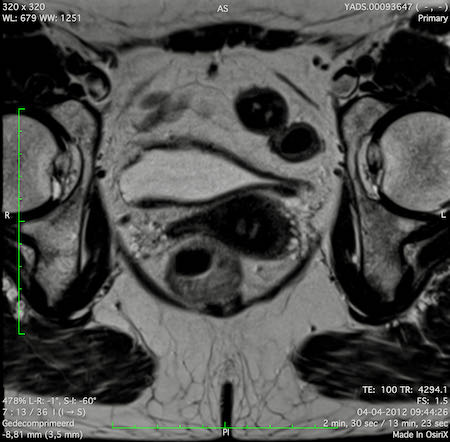

Hình ảnh

Các hình ảnh được cung cấp cho thấy ung thư biểu mô tế bào nhẫn với tình trạng dày lan tỏa thành trực tràng, hình ảnh bia bắn điển hình, và sự xâm lấn mỡ mạc treo trực tràng.